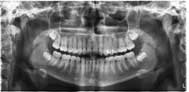

Radiographie Panoramique Dentaire |

| Il s’agit d’une vue d’ensemble de face de toute la mâchoire,

dents et articulations. |

| L’examen est réalisé debout, le menton et le front positionnés

dans le plan vertical. |

| La rotation du tube dure vingt secondes. |

Il

donne d’excellents renseignements sur le nombre et la position

des dents, les caries, les dépôts de tartre, l’épaisseur

de l’os, l’état des articulations.

Un

cliché et un CD sont remis au patient. |